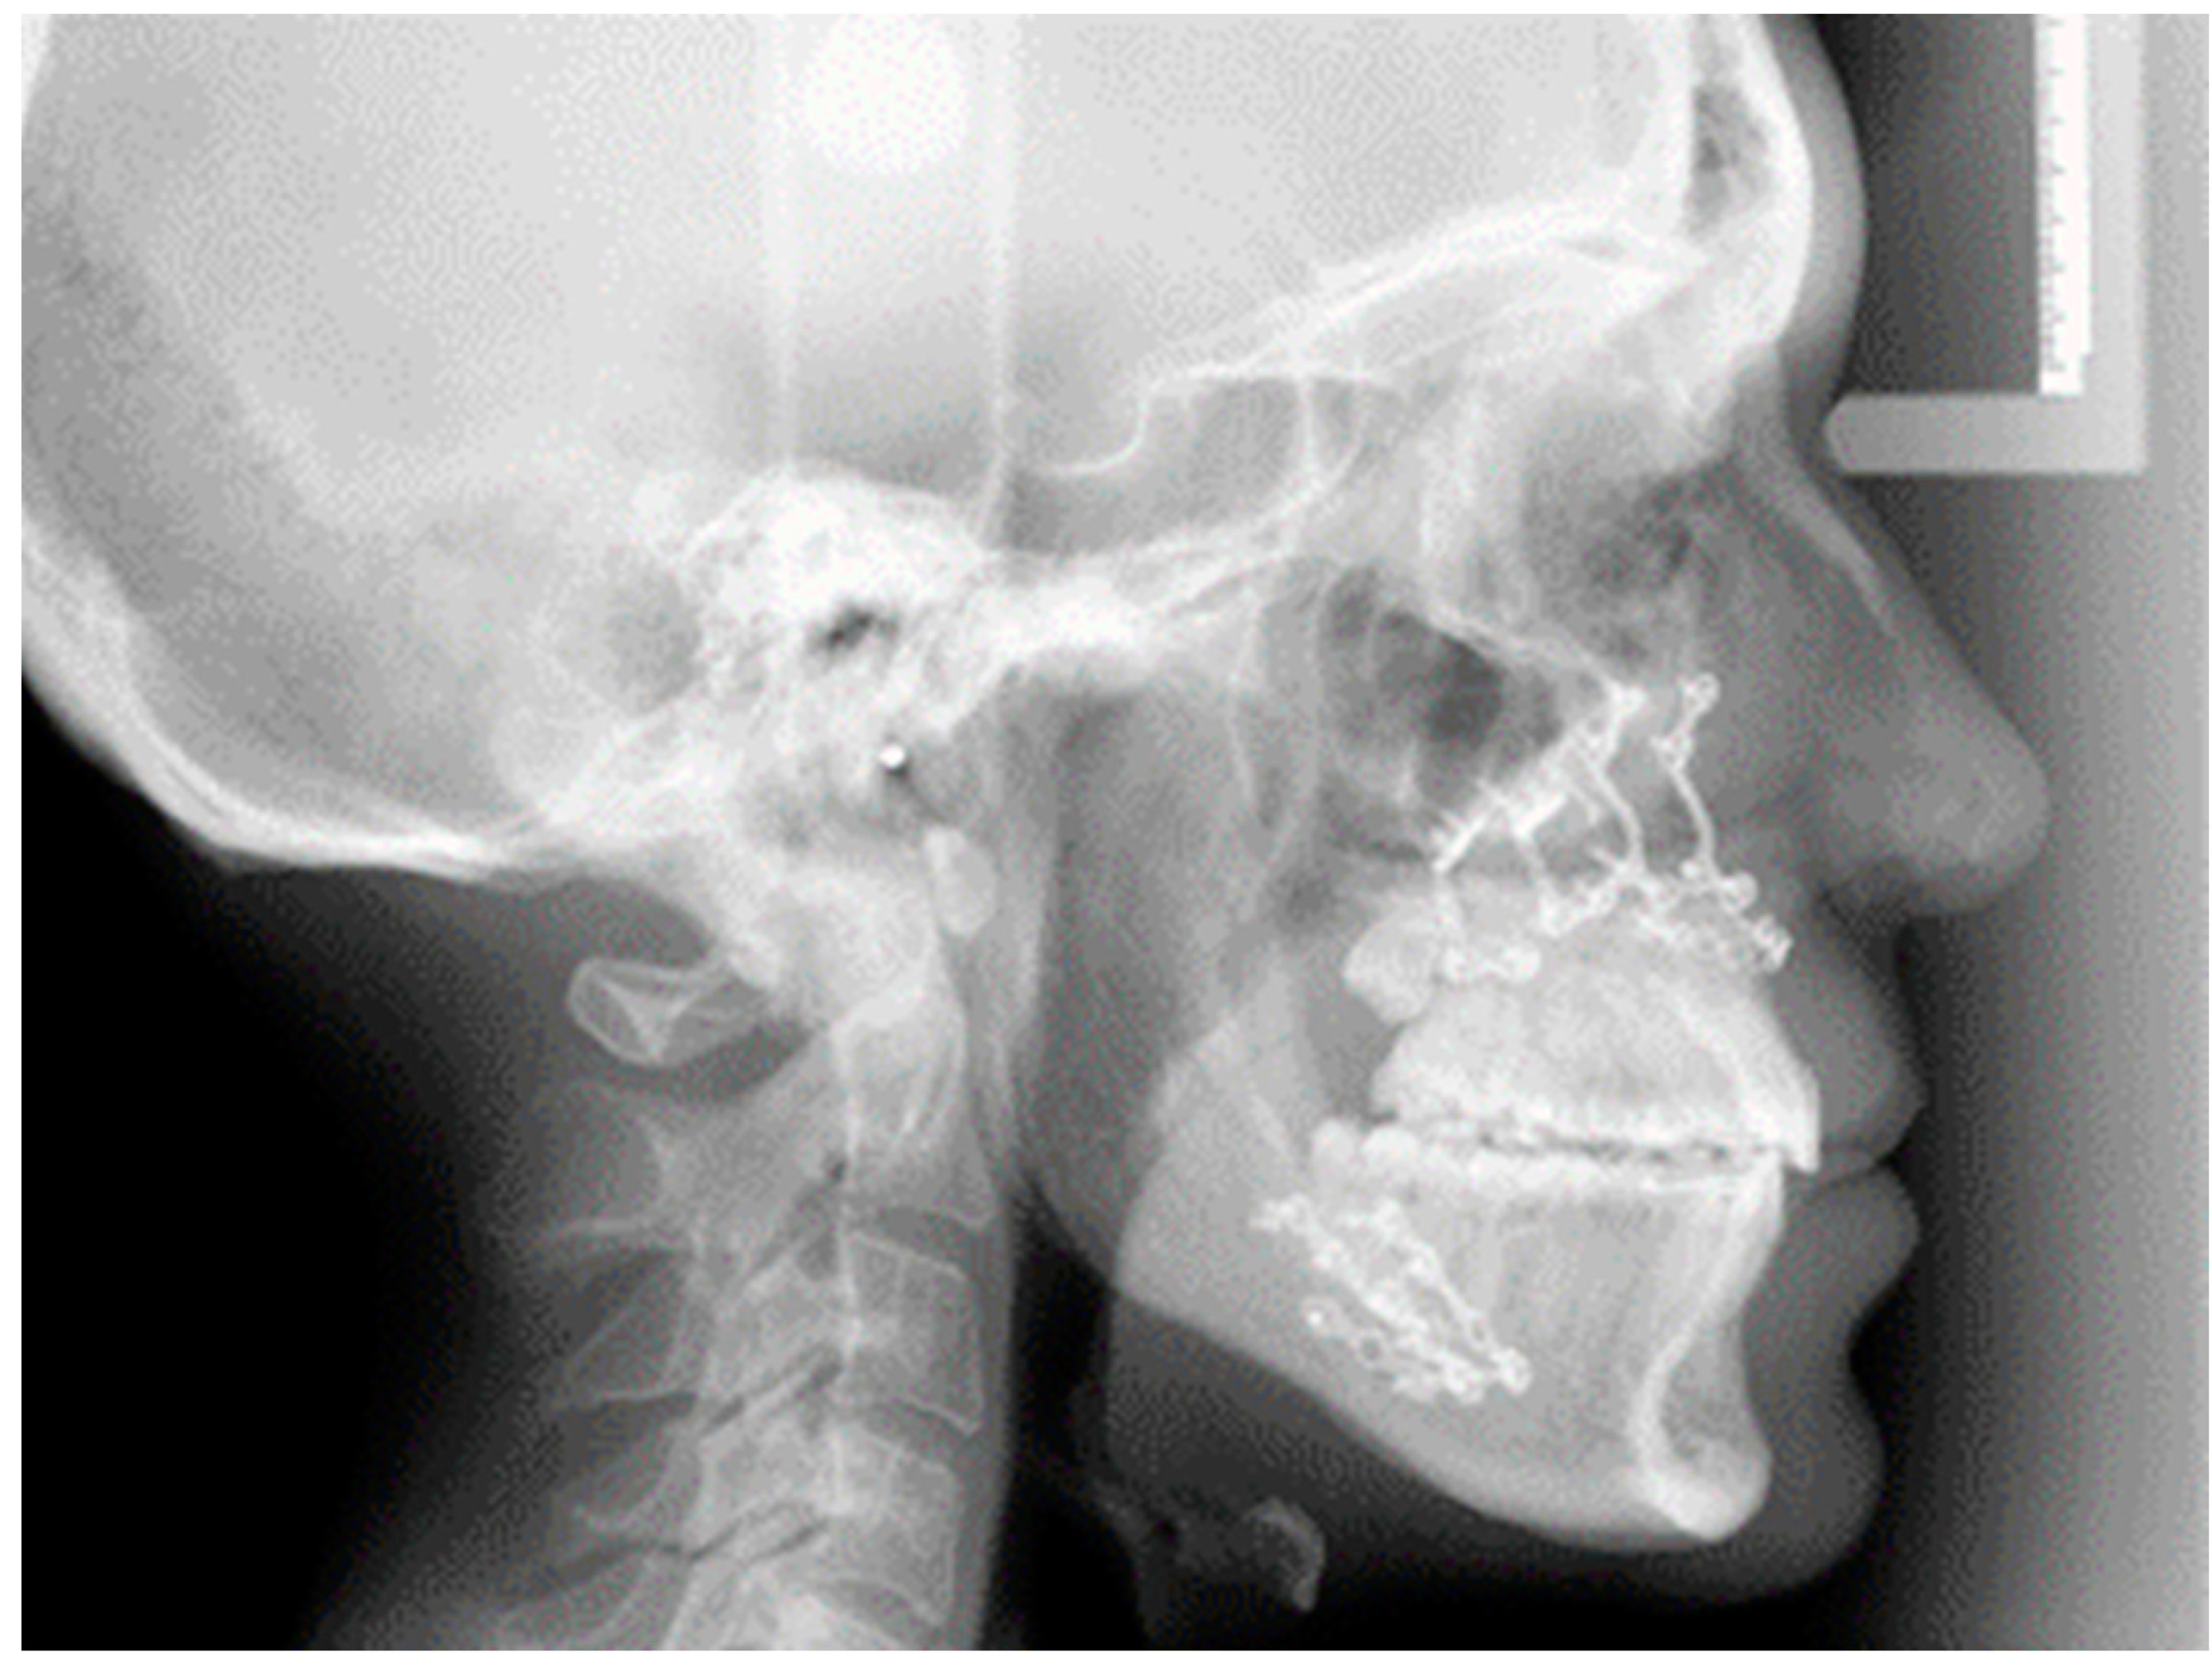

2.1. Digital Surgical Planning

2.2. Evaluation of the Surgical Accuracy